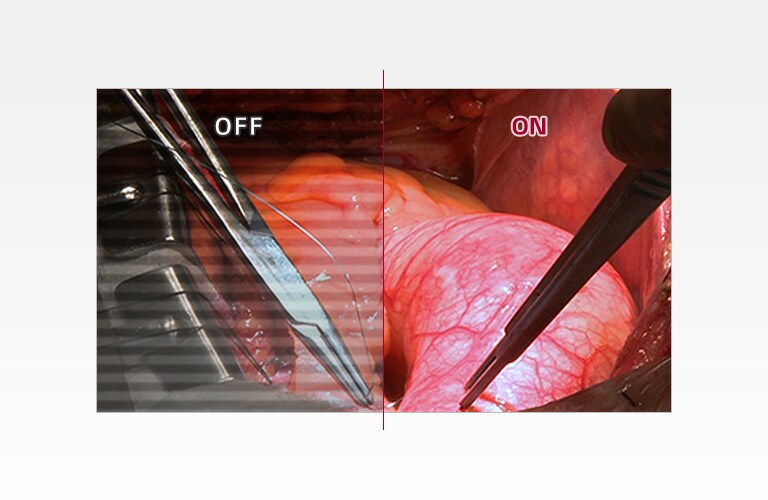

sRGB 115% (Area), sRGB over 99% (Coverage)